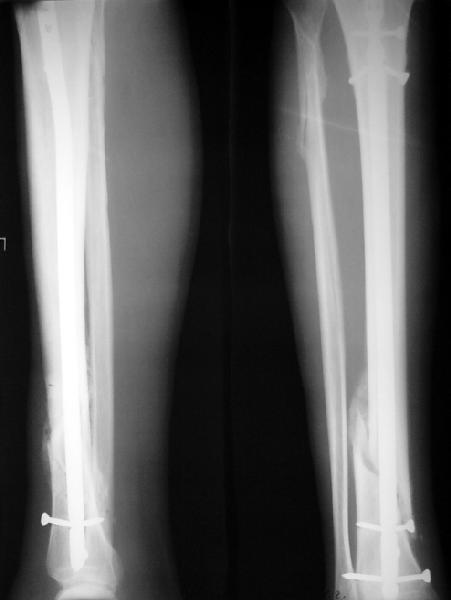

Как мне показать пример? Фото стоящего на одной оперированной конечности пациента? O! Пример, подвигнувший нас на некоторое изменение технологий. Пациент этот ходил с полной нагрузкой вопреки рекомендациям. В качестве подтверждения - сломанный проксимальный статический винт к 1 мес., а к 2 мес. - все остальные. Сейчас мы перешли на более fool-proof остесинтез.

На мой взгляд, на снимках, приведённых Вами - неправильно сростающийся перелом дистальной трети большеберцовой кости, состояние после остеосинтеза интрамедуллярным гвоздём.

Как Вы пишите снимок под номером 1 - менсяц после операции, под номером 2- два месяца после операции.

Вы не послали послеоперационный снимок, поэтому трудно судить о состоянии редукции после операции.

I think that the X-Rays show S/P IMN of Spiral # of the Distal Tibia consoles in misalignment.

You wrote that a picture number 1 - f month after the surgery, and number 2-two months after the surgery.

You have not sent a postoperative X-Rays; so it's impossible to discuss about the condition of a reduction after operation.